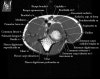

팔꿈치 관절의 MRI 단면 영상

2. Axial section

1) The tendons of the Biceps Brachii and Brachiallis muscles transversely as they insert onto the Radius and Ulna respectively. 2) The distal Triceps tendon is also well evlauated in this plane.